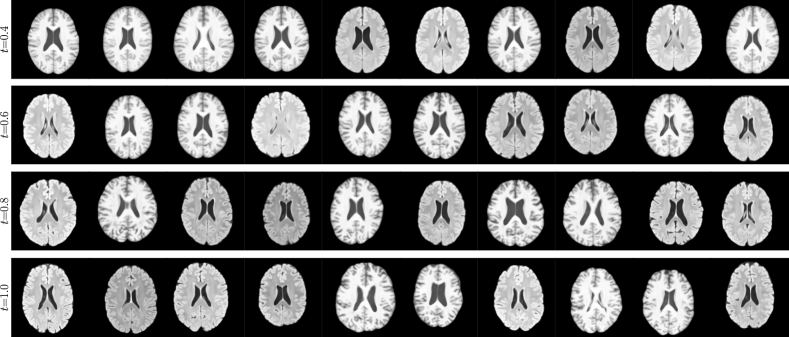

4 Experiments

We present 3 case studies on counterfactual inference of high-dimensional structured variables111https://github.com/biomedia-mira/causal-gen. To quantitatively evaluate our deep SCMs, we measure effectiveness and composition, which are axiomatic properties of counterfactuals that hold true in all causal models (Pearl, 2009; Monteiro et al., 2023). Effectiveness is measured via the anticausal parent predictors from Section 3.4, and composition is measured via the distortion of ’s HVAE mechanism upon null-interventions. Please refer to Appendix B for more details.

4.2 Brain Imaging Counterfactuals

To demonstrate our model’s ability to produce faithful high-fidelity counterfactuals of real data, we extend our approach to a real-world scenario involving brain MRI scans from the UK Biobank (Sudlow et al., 2015). As before, we start with an assumed causal generative process involving a set of observed variables as shown in Figure 4(a). The causal graph is medically informed and extends the scenario in Pawlowski et al. (2020) by: (i) introducing an additional MRI Sequence (T1/T2) binary variable to enable discrete counterfactuals; (ii) having directly. We used a scaled-up version of our exogenous prior HVAE as ’s mechanism and used (conditional) normalizing flows for the other mechanisms (see Appendix A.1). As shown in Figure 4, our deep SCM is capable of producing qualitatively sharp counterfactuals with localised changes according to the intervened upon parent(s) and the associated causal graph. Importantly, the identity of subjects is well preserved in all cases including null-interventions (i.e. nothing). Table 2 shows the counterfactual effectiveness results from random interventions on each variable. We observed satisfactory initial counterfactual effectiveness and significant improvements of post counterfactual training, demonstrating the merit of the proposed approach. Please refer to Appendix A.2 for notes on abduction uncertainty and D for additional results.